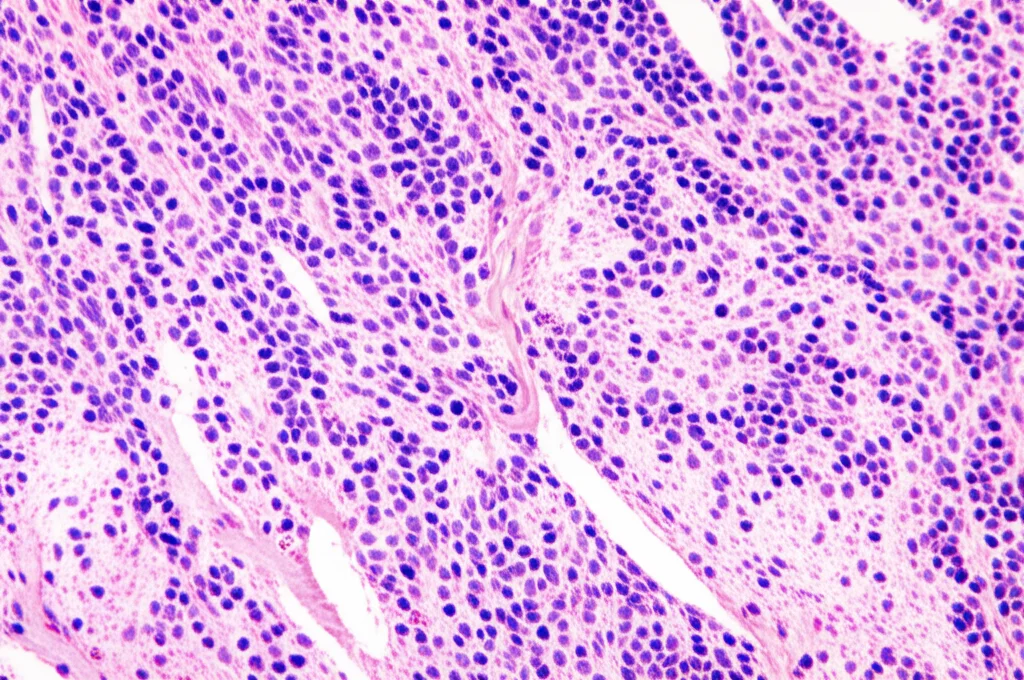

Il tumore primario resta un fantasma. Si procede allora con una biopsia della massa linfonodale. L’analisi al microscopio rivela cellule tumorali grandi, “brutte” (pleomorfe, con nucleoli evidenti), indicative di una neoplasia poco differenziata. Ma quali?

Qui entra in gioco l’immunochimica (IHC), una tecnica che usa anticorpi specifici per “colorare” determinate proteine presenti (o assenti) nelle cellule tumorali, aiutandoci a capire la loro origine e natura. È come dare un’identità precisa a queste cellule impazzite. I risultati sono illuminanti: le cellule sono positive per marcatori come AE1/AE3, EMA e, soprattutto, INSM1. Quest’ultimo è un marcatore abbastanza specifico per la differenziazione neuroendocrina. Altri marcatori (per linfomi, melanomi, carcinomi squamosi, ecc.) sono tutti negativi. Inoltre, l’indice di proliferazione Ki-67 è altissimo (88-90%), segno di un tumore molto aggressivo.

La diagnosi è fatta: Metastasi linfonodale di carcinoma con differenziazione neuroendocrina. Un evento rarissimo, specialmente senza un primario identificabile!